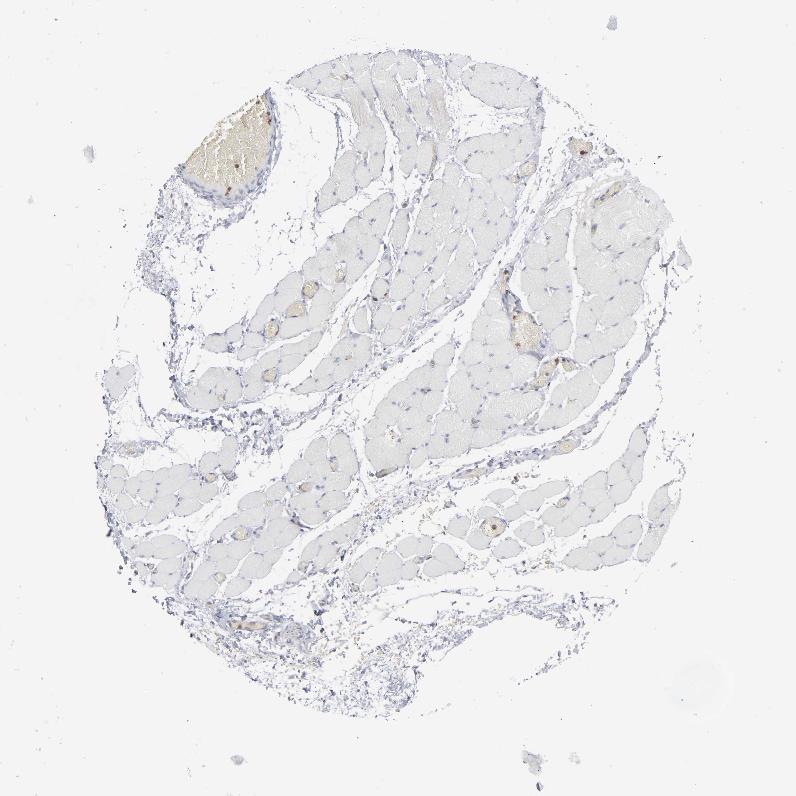

SKELETAL MUSCLE - Antibody stainingi

Antibody staining in the annotated cell types in the current human tissue is reported as not detected, low, medium, or high, based on conventional immunohistochemistry profiling in selected tissues. This score is based on the combination of the staining intensity and fraction of stained cells.

Each image is clickable and will lead to virtual microscopy that enables deeper exploration of all samples and also displays staining intensity scores, fraction scores and subcellular localization as well as patient and tissue information for each sample.

Antibody HPA008467Antibody HPA041113Antibody CAB002169Antibody CAB076057

Myocytes MediumNot detectedNot detectedNot detected